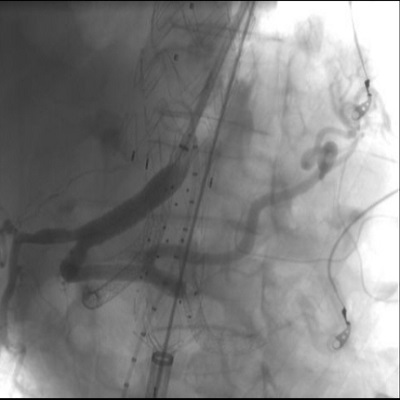

Di recente la U.O.C. Chirurgia Vascolare del Grande Ospedale Metropolitano di Reggio Calabria ha eseguito con successo un trattamento di elevata complessità su un paziente con un voluminoso aneurisma toraco-addominale (7 cm di diametro).

L’aneurisma toracico è stato trattato con un approccio endovascolare, mediante il posizionamento di endoprotesi; successivamente è stata posizionata un’endoprotesi ramificata per i vasi viscerali ed una terza endoprotesi aorto-bisiliaca. Il decorso post-operatorio è stato ottimale: il paziente non ha avuto complicanze ed è stato dimesso al proprio domicilio in buone condizioni di salute.